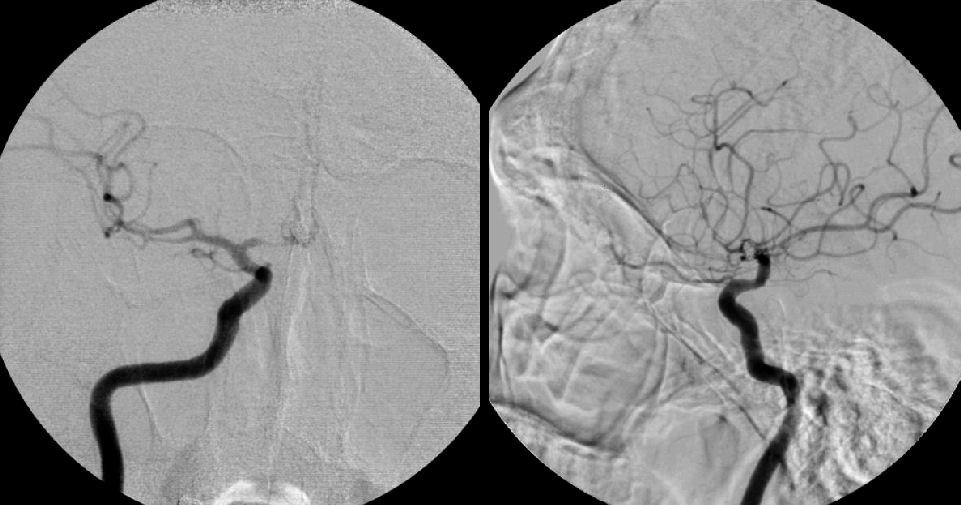

Điều trị lập lại lưu thông cho ống tiêu hóa bằng điện quang đã được ứng dụng tại nhiều nước trên thế giới. Theo định nghĩa, hệ thống chụp mạch máu số hóa xóa nền (DSA) là phương pháp chẩn đoán kết hợp giữa chụp X-quang và xử lý hình ảnh số để chụp mạch trong cơ thể. Những ưu điểm nổi bật của phương pháp này dưới hướng dẫn chụp số hóa xóa nền là: